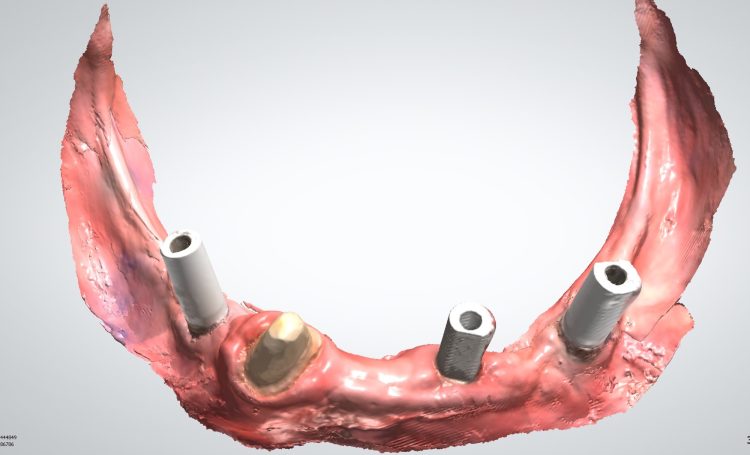

Teleskopierende Brücken im digitalen Ablauf hergestellt.

Implantatbrücke zur Wiederherstellung der Zahn- und Zahnfleischanteile mit verschraubten Brücken.